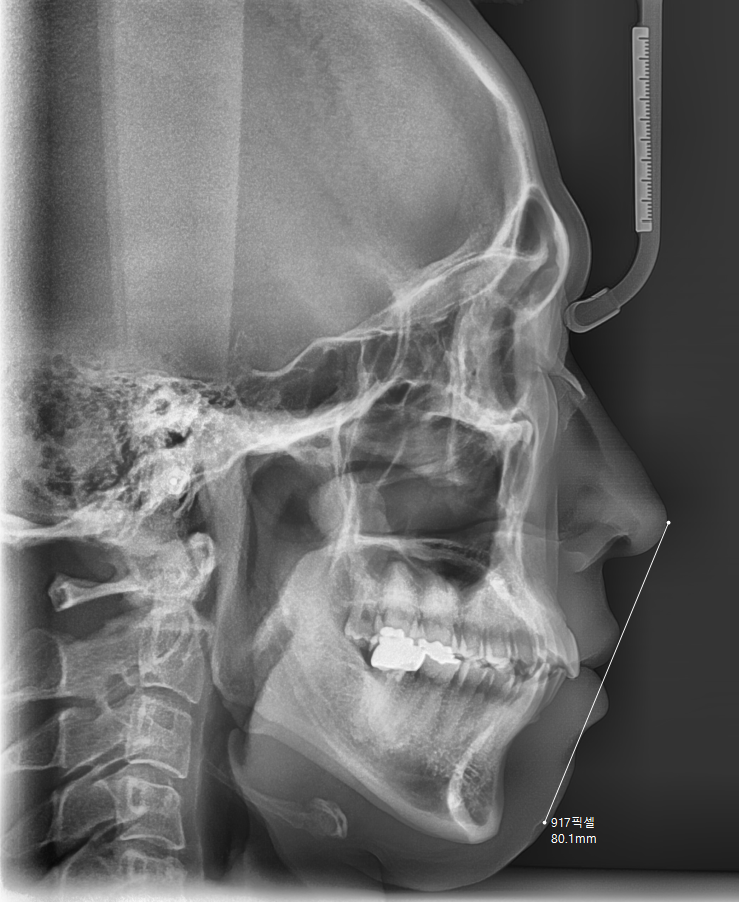

물론 성인의 경우 뼈 성장이 완료했기 때문에

치료 기간이 청소년보다 조금 더 길 수 있습니다.

노화가 시작되기 때문에 잇몸과 뿌리의 유연성이 떨어지거든요

그래서 조심스럽게 진행해야하는 것도 맞고

잇몸 상태를 계속 체크도 필요해요

x-ray, 구강 상태, 교합 확인

다양한 검사를 시행